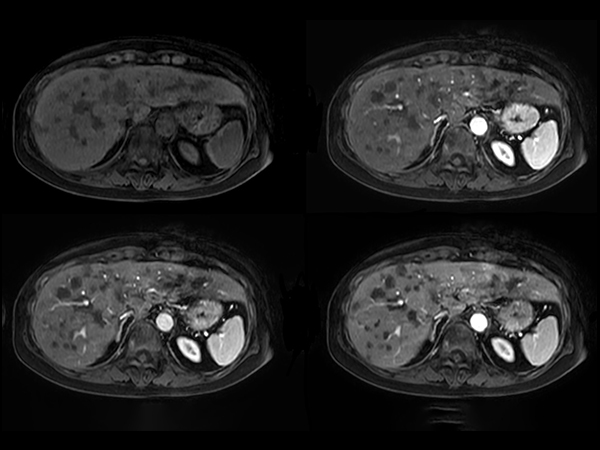

Axial Dynamic eTHRIVE

Axial eTHRIVE 90 sec Post gado

Axial eTHRIVE 2 min Post gado

Axial eTHRIVE 3 min Post gado

Axial eTHRIVE 15 min Post gado